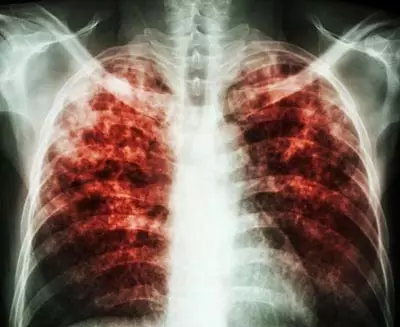

慢阻肺肺氣腫總是治不好?你可能踩到了這三大雷區(qū)!

慢阻肺跟高血壓一樣也是一種慢性病,早期治療事半功倍,長期而有計(jì)劃的綜合治療是治療疾病的關(guān)鍵所在。

為什么慢阻肺頻頻治療總不好?

其實(shí),慢阻肺跟高血壓一樣也是一種慢性病,早期治療事半功倍,長期而有計(jì)劃的綜合治療是治療疾病的關(guān)鍵所在。

慢阻肺屬于冬病,冬天容易發(fā)作。而現(xiàn)在是夏天,多數(shù)患者的病情處于穩(wěn)定期,各種癥狀都比較輕。大部分慢阻肺患者卻忽略了治療,錯失了良機(jī)。有種說法是“急性加重期是救命的,穩(wěn)定期才是治病的”,因此提倡大家冬病夏治。

慢阻肺肺氣腫是慢性病,需要慢慢治療?;颊邞?yīng)該有計(jì)劃地綜合性的長期治療,以達(dá)到防微杜漸的作用,減緩疾病發(fā)展的速度,減少急性發(fā)作和并發(fā)癥的發(fā)生。

所以,治療肺氣腫、慢阻肺這些慢性病,切莫錯失良機(jī),不可急于求成,更不能見好就收。關(guān)鍵在于長期堅(jiān)持疏通氣道、排出黏痰、排出二氧化碳,輕輕松松就能在家治療,減少發(fā)病,減少住院。